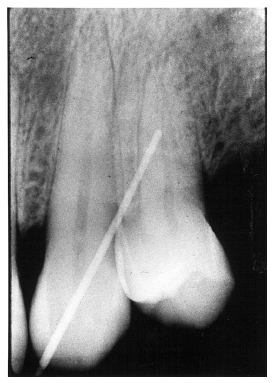

Clinically, the extensive bone loss and gingival recession of advanced periodontal disease may be easily visualized. In less advanced cases, the periodontal probe can be used to measure the distance between the gingival crest and the periodontal attachment. Bleeding at the point of probing and measurement of significant distances are strong indications of periodontal disease. Figure 6 radiographically illustrates probe depth in a case of moderate periodontal disease with early alveolar bone loss.

Figure 6 - Probe Depth in Moderate Periodontal Disease

Figure 6